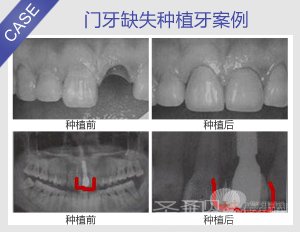

门牙缺失 圣贝种植系统给您自信

检查:门牙缺失一颗。X线检查显示缺牙区牙槽骨未愈合,牙槽窝内有血坏凝结

种植方案:结合肤色、脸型,采用种植牙修复进行治疗

种植技术:Prussian即刻种植系统

种植后:牙齿排列整齐,牙色洁白自然。种植完毕,患者十分满意。

到诊后,朴东信院长为王同学进行了详细检查,其结果为:门牙缺失一颗。X线检查显示缺牙区牙槽骨未愈合,牙槽窝内有血坏凝结。

由于王同学的家长一再要求为该患者使用最好的镶牙方式进行治疗。因此朴东信院长在征得王同学家长的同意,并签署治疗合同后,为王同学采用种植牙修复进行治疗。